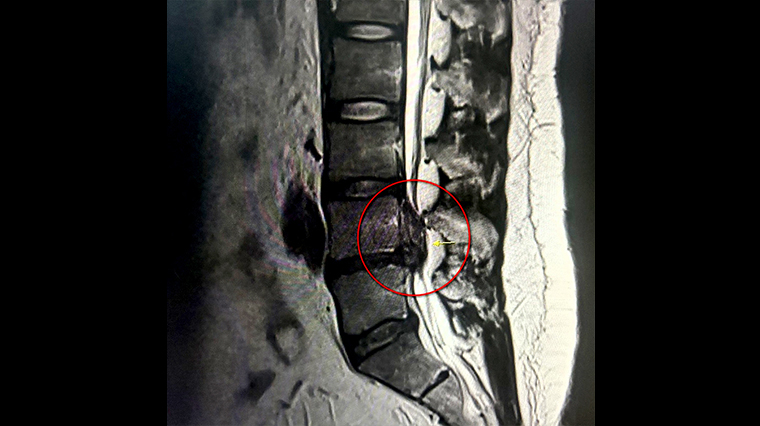

▲根據檢查結果,魏先生的第4、5節約有4公分大的椎間盤突出,嚴重壓迫神經。(圖/台北慈濟醫院提供)

【NOW健康 陳郁茹/新北報導】30歲的魏先生體重超過100公斤,先前因椎間盤突出,採取復健及藥物治療半年之久,但無明顯改善,他在1個月前疼痛加劇,開始雙腳無力、頻繁跌倒,走路約5分鐘就需坐下休息,大幅影響生活品質。魏先生後來到大醫院接受核磁共振掃描檢查,發現腰椎第4、5節約有4公分大的椎間盤突出,在考量工作需求後,接受「微創脊椎內視鏡手術」治療,術後第2日便順利出院,隔日正常上班,生活重回正軌。